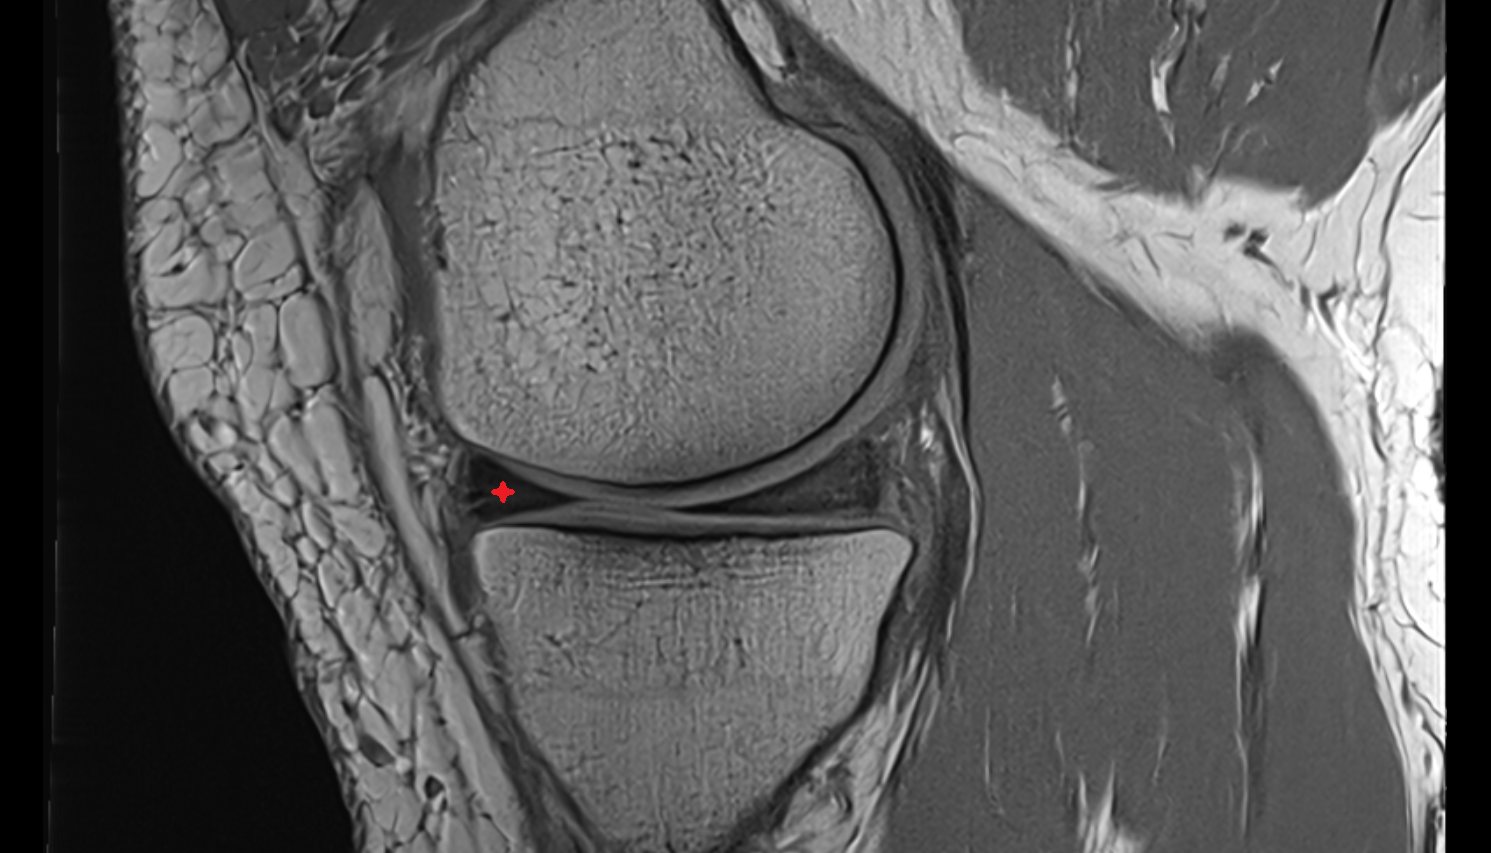

- Medial collateral ligament

- Medial meniscus

- Anterior horn of medial meniscus

- Posterior horn of medial meniscus

- Body of medial meniscus

- Anterior root of medial meniscus

- Posterior root of medial meniscus